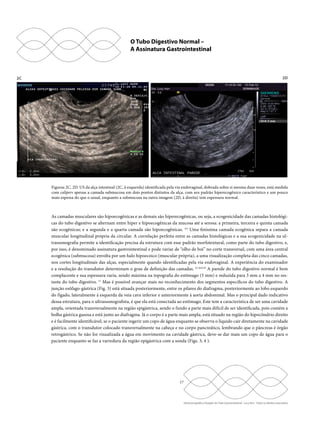

Figuras 8A, 8B. US do jejuno. As imagens mostram o característico pregueamento das válvulas coniventes pela via transabdominal

(8A, à esquerda) e pela via transvaginal (8B, à direita), onde é possível identificar a assinatura gastrointestinal com maior facilidade,

com sua fina camada submucosa.